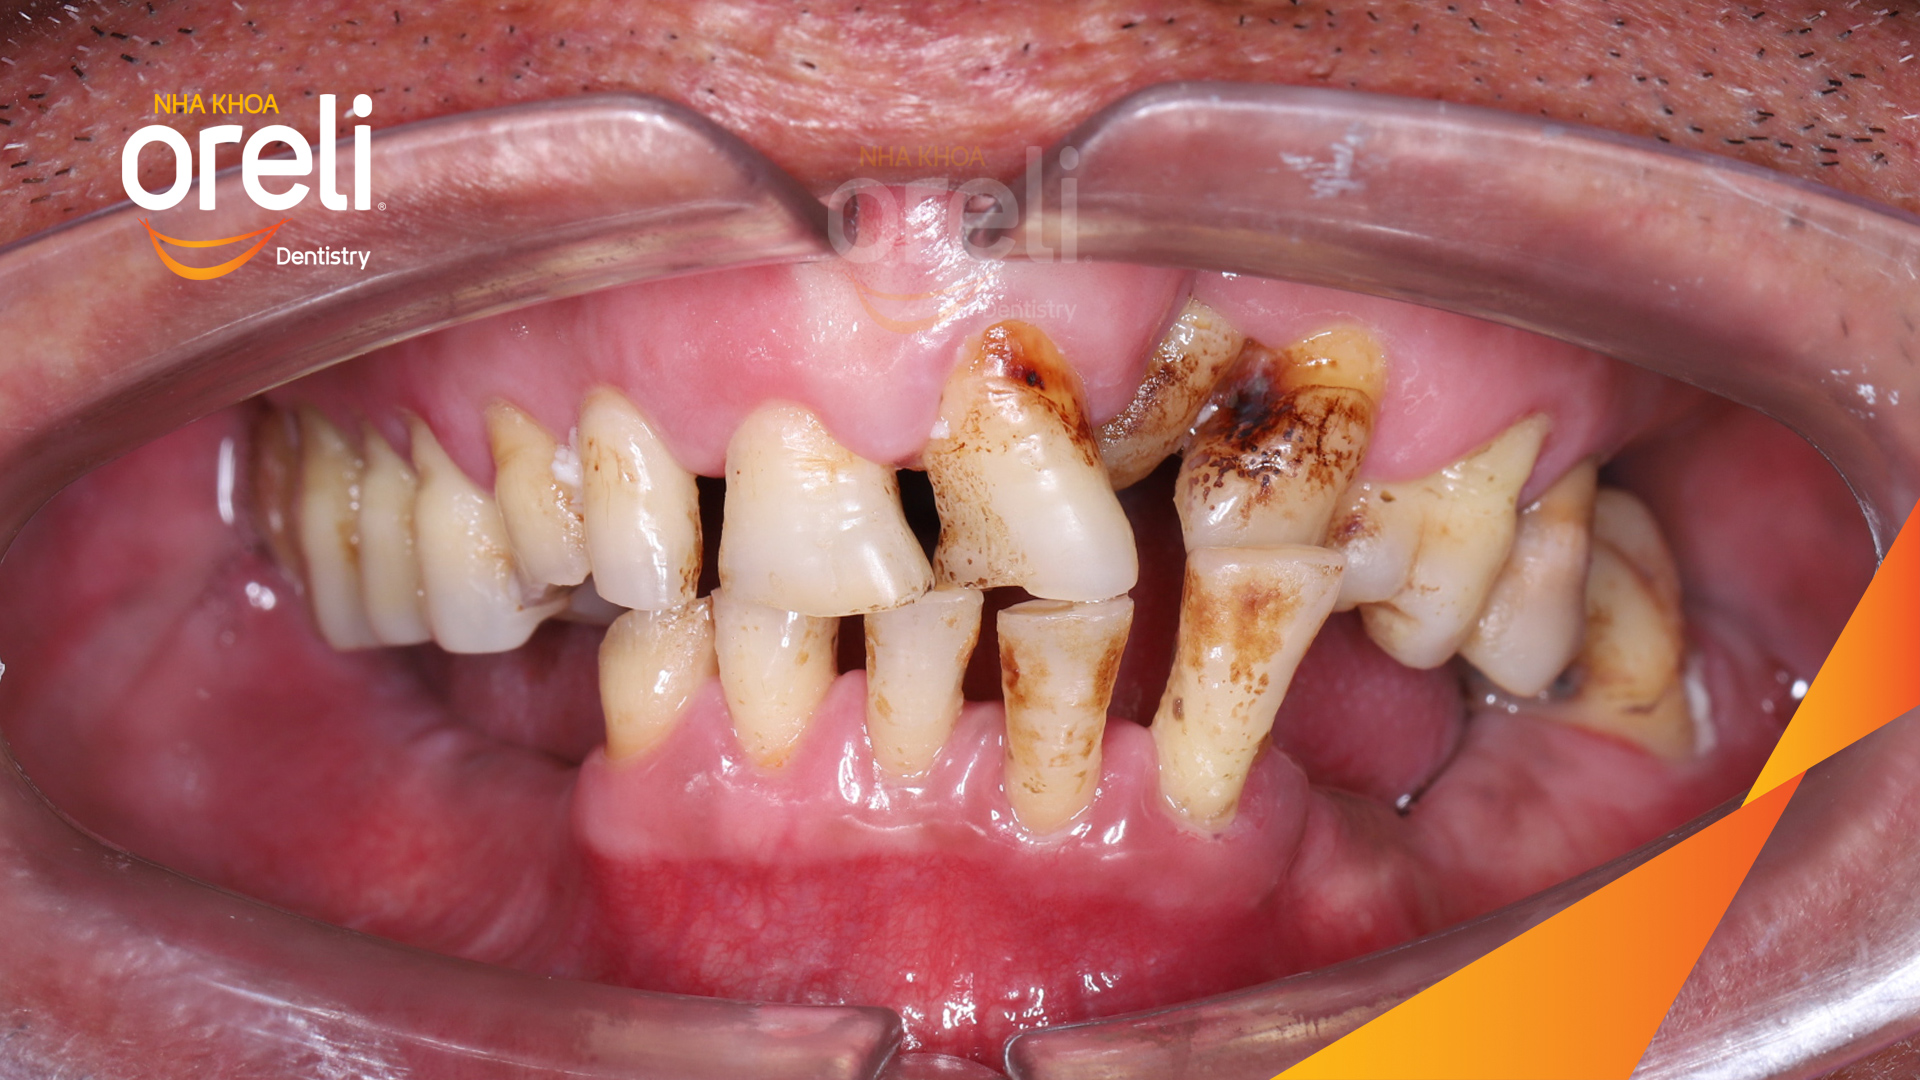

Tình trạng: Mất răng vùng răng sau hàm dưới, các răng trước lung lay mất khả năng hồi phục

Giải pháp: Nhổ răng trồng răng implant hàm dưới và hai răng hàm trên